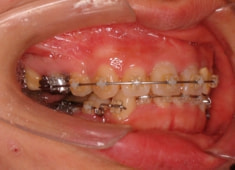

治療後(3年2ヶ月後)

治療開始から1年8ヶ月後